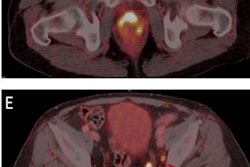

Examples of individual minor and major therapeutic change in patients with biochemical recurrence after radical prostatectomy undergoing F-18 rhPSMA 7.3 PET/CT examination.

(B, E) 57-year-old patient presenting with biochemical recurrence (PSA = 1.0 ng/mL) seven years after radical prostatectomy. Fused F-18 rhPSMA 7.3 PET/CT shows focal PSMA ligand uptake in an unsuspicious lymph node adjacent to the left external iliac artery suspicious for singular lymph node metastasis. Therapeutic management was changed from radiation therapy of the prostatic bed and additional short-term androgen deprivation therapy to salvage lymphadenectomy.